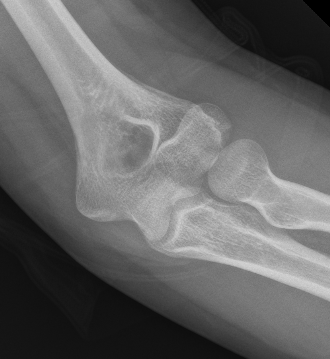

Double arc sign seen on xray

Double arc sign on xray

Bryan & Morrey Classification

Type I Type II

Large osseous fracture of the capitellum

Articular cartilage injury with little bone

Hanh Steinthal fracture

Kocher Lorenz fracture